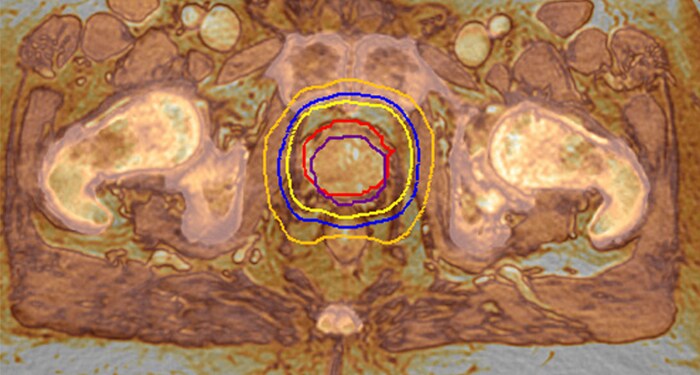

MRCAT Prostate + Auto-Contouring

As a plug-in clinical application to Ingenia MR-RT, MRCAT Prostate + Auto-Contouring provides attenuation maps and automated, MR-based contours of prostate and organs at risk in as little as 20 minutes – all in a repeatable ‘one-click’ workflow.

MRCAT Pelvis lets you plan radiation therapy using MRI as a single modality solution. Within just one MR exam, MRCAT Pelvis provides excellent soft-tissue contrast for target and OAR delineation, and continuous Hounsfield units for dose calculations. MRCAT (MR for Calculating ATtenuation) data can be used for export to treatment planning systems for CT-equivalent** dose calculations. In addition, MR-based imaging enables CBCT-based positioning based on soft-tissue contrast with the look and feel of CT.